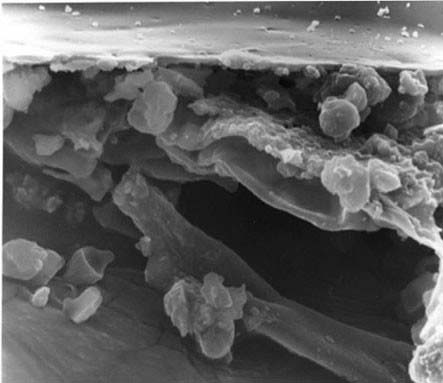

سلولهای بنیادی مغز استخوان انسان